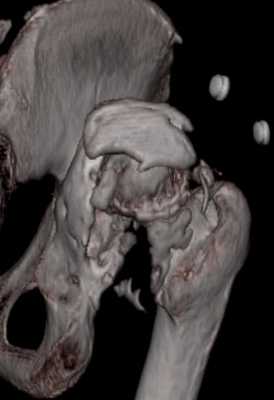

На последнем срезе КТ задний край практически отсутсвует по сравнения со здоровой стороной. Разумеется, что это плоскостное изображение, но головка вывихнулась не только в плоскостную щель захваченную на КТ. Если вы считаете, что удастся установить туда чашку даже низкопрофильную, остается пожелать вам успехов. Но перед этим можно смоделировать установку чашки на скиаграммах КТ.

За пожелание успехов - спасибо, думаю это пригодится, не очень понял про плоскостную щель, специально предоставил срезы на уровне свода - он цел, дефект заднего края ниже, за счет заглубления он будет еще меньше, по данным 3d - должно получиться.

Решение по ВВ придется принимать по месту.... Сумеете "подрыться" и получить хорошее покрытие чашки (+2 винта об-но) - хорошо, если нет -

костная аутопластика из головки.